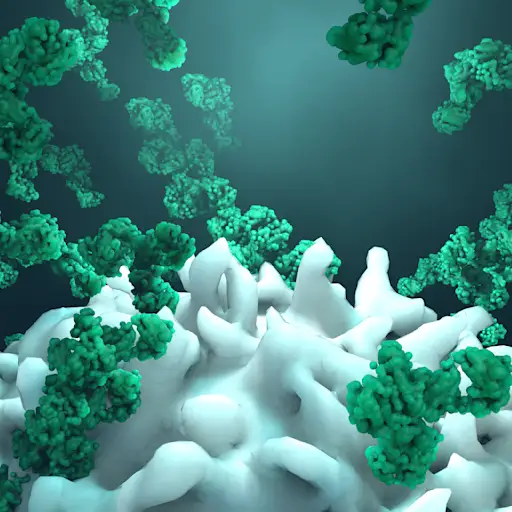

谬论:晚期非小细胞肺癌是死刑判决

统计数据是严峻的。美国癌症协会估计,被诊断为转移性非小细胞肺癌的患者中,只有7%的人能活过五年。但是,罗德里格斯医生说,这个数字包括那些没有接受治疗或没有接受最新治疗的人,比如免疫疗法,它利用你的免疫系统来对抗你的癌症。罗德里格斯医生说,五年存活率攀升至25%,而且还在继续上升。她说:“这仍然不够长,但这是以前没有见过的。”“免疫疗法是游戏规则的改变者。”